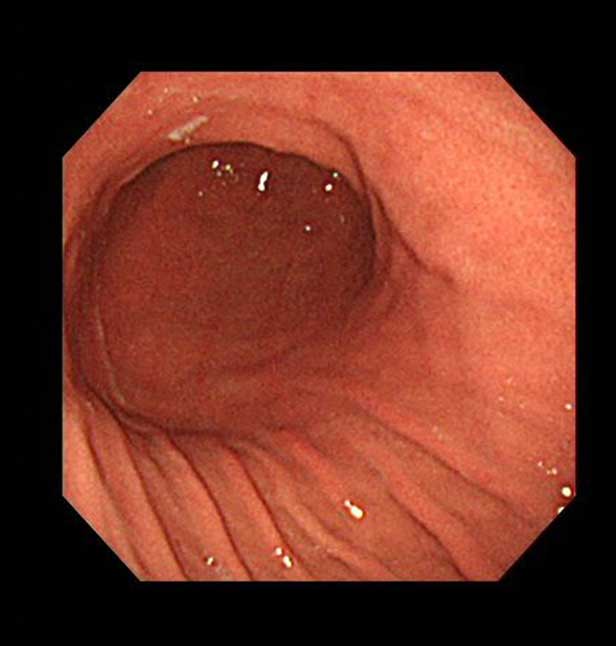

まずは上部消化管内視鏡検査(胃カメラ)で、胃粘膜の萎縮の程度や広がりを観察します。

萎縮した粘膜は白っぽく抜けていたり、血管が透けて見えたりします。

ピロリ菌感染による胃炎の場合は、このほか、むくんだ感じに見えたり、しわ(皺襞:すうへき)が太くなり、点状もしくは斑状に赤くなったりします。

胃液の分泌が低下するために、粘膜の表面に直接胃酸が触れてただれます。

また、細い静脈の集合が規則的に配列する、RAC(regular arrangement collecting)という点状の発赤(ほっせき:赤み)が消失します。

萎縮部分の粘膜が鳥肌のように凸凹することもあります。

このような内視鏡所見ではピロリ菌感染を疑い、ピロリ菌検査を同時に行います。